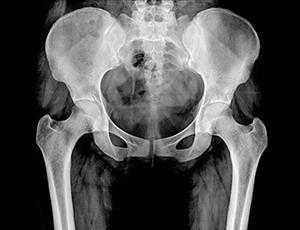

Таз представляет собой часть скелета, которая расположена в основании позвоночного столба. Он не только является опорой для внутренних органов, но и обеспечивает фиксацию к туловищу ног. Именно поэтому его здоровье играет немаловажную роль, а рентген костей таза является неотъемлемой составляющей диагностики при заболеваниях и травмах этой области.

Он является диагностическим высокоинформативным методом, позволяющим получить данные о состоянии костных структур и суставов таза, определить повреждения и патологии мягких тканей и внутренних органов. Рентгенографию широко применяют в поликлиниках, поэтому она является доступным методом, в том числе и в ценовом плане. Пройти рентген костей малого и большого таза можно в диагностическом центре многопрофильной клиники ЦЭЛТ. Мы располагаем современным оборудованием, а наши специалисты практикуют индивидуальный подход, что неизменно позволяет добиваться высокого качества рентгенографических снимков.

Тазобедренный сустав является сложным многоосным сочленением, которое выполняет сгибание/разгибание, отведение/приведение, пронацию и супинацию бёдер и принимает на себя серьёзную нагрузку. Любые нарушения в его функционировании не только приводят к серьёзному дискомфорту для человека, но и могут стать причиной развития серьёзных нарушений. Рентген тазобедренного сустава (ТБС) — это неинвазивный диагностический метод, ценность которого сложно переоценить.

Он нашёл широкое применение в разных областях медицины, включая травматологию, ревматологию, ортопедию, гнойную хирургию для диагностики заболеваний и последствий перенесённых травм, для определения объёма предстоящей операции или эффективности проведённого лечения. Процедура достаточно безопасна, высокоэффективна и проста, но при этом позволяет получить ценные данные о состоянии ТБС пациента.